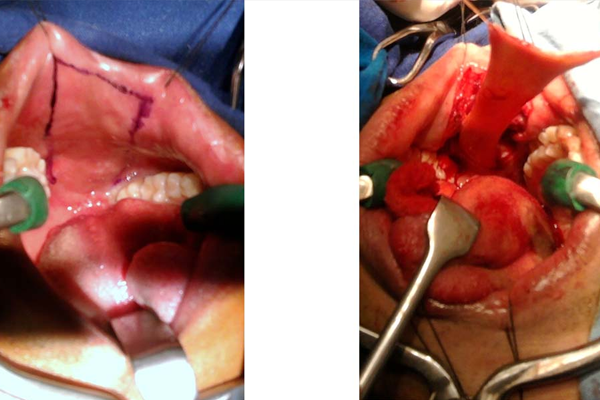

HARVESTING BUCCAL MUCOSA FOR FULL LENGTH BARBAGLI’S URETHROPLASTY

Mr Shyam Meena (name changed) 29 yr a young boy employed in a shipping company. He was trapped between a metallic door in a submarine and sustained a crush fracture of the pelvis. He developed retention of urine with urethral bleeding. Underwent emergency surgery for pelvic brim (pelvic girdle) fixation and suprapubic catheterization. He was not able to pass urine through the urethra because of complete disruption at the level of the prostatomembranous urethra. He approached me and then after evaluation, the diagnosis of PFUDD (pelvic fracture urethral distraction defect) was made. He underwent a successful urethroplasty.